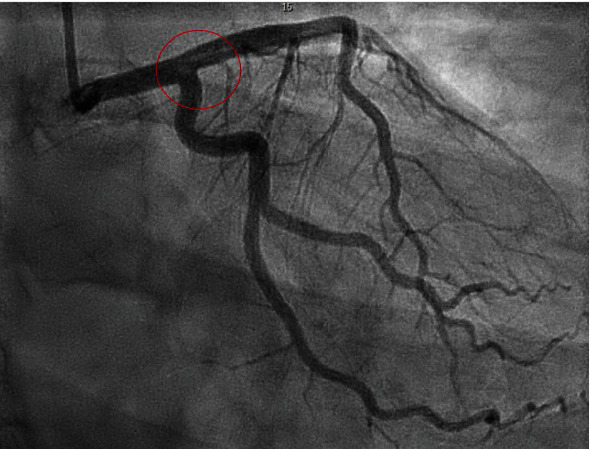

Coronary angiogram revealed a saddle clot (thrombus) involving the distal left main artery, left circumflex, and proximal LAD (Figure 2). TIMI flow grade was 3 throughout, and no intervention took place during the coronary angiogram. There was also an occlusion in the apical portion of the LAD. The right coronary artery did not have any abnormalities. An echocardiogram revealed an estimated ejection fraction of 55-60% with apical septal hypokinesis and a normal diastolic function. There was no evidence of an intra-atrial shunt or left atrial appendage. Patient was admitted to the cardiac care unit (CCU) and was started on intravenous tirofiban for 10 hours, oral aspirin 81 milligrams daily, oral clopidogrel 75 milligrams daily, and intravenous heparin drip as per ACS protocol. Troponin peaked at 11 ng/mL. The patient was given 2 units of PRBC due to persistent vaginal bleeding. Doppler of the lower extremities did not reveal any evidence of a DVT. Telemetry over 48 hours of the hospital stay did not show any evidence of cardiac arrhythmia.

Figure 2.

Coronary angiogram revealed a saddle clot (thrombus) involving the distal left main artery, left circumflex artery, and proximal left anterior descending artery (red circle).